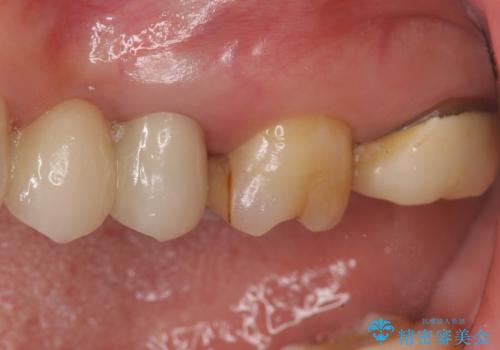

向かい合わせの歯の咬みこみが強くインレーよりも強度の高いクラウンでの治療となりました。その中でも色が白くある程度の薄さでも耐久性を発揮するフルジルコニアクラウンでの修復を行いました。適合も良く色調もとてもなじんだため大変喜んでいただけました。